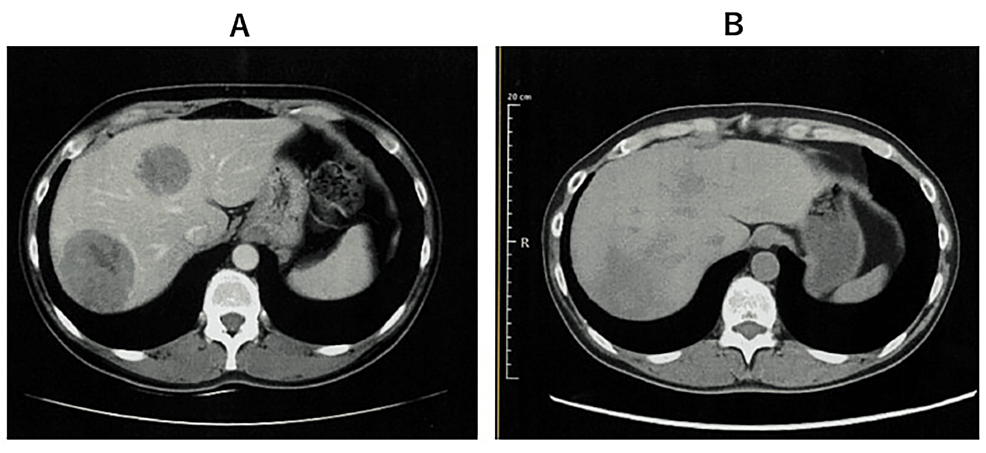

在中国,非小细胞肺癌(NSCLC)是发病率和死亡率最高的恶性肿瘤。其中,约40%-50%的肺腺癌患者携带表皮生长因子受体(EGFR)基因突变。

近日,《Neuro-Oncology》在线全文发表了埃克替尼联合阿美替尼一线治疗EGFR突变伴脑转移非小细胞肺癌患者的疗效与安全性的一项I/II期临床研究的研究结果。